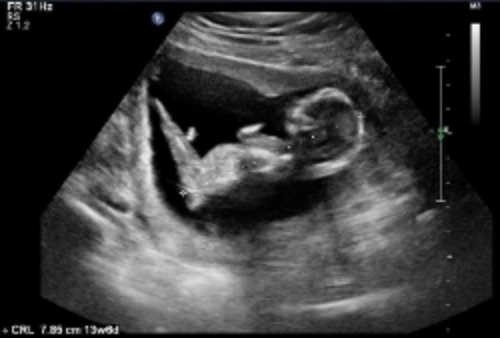

Here are some u/s pics from my friend at 13 weeks. Any nub guesses?

Attachment 24160